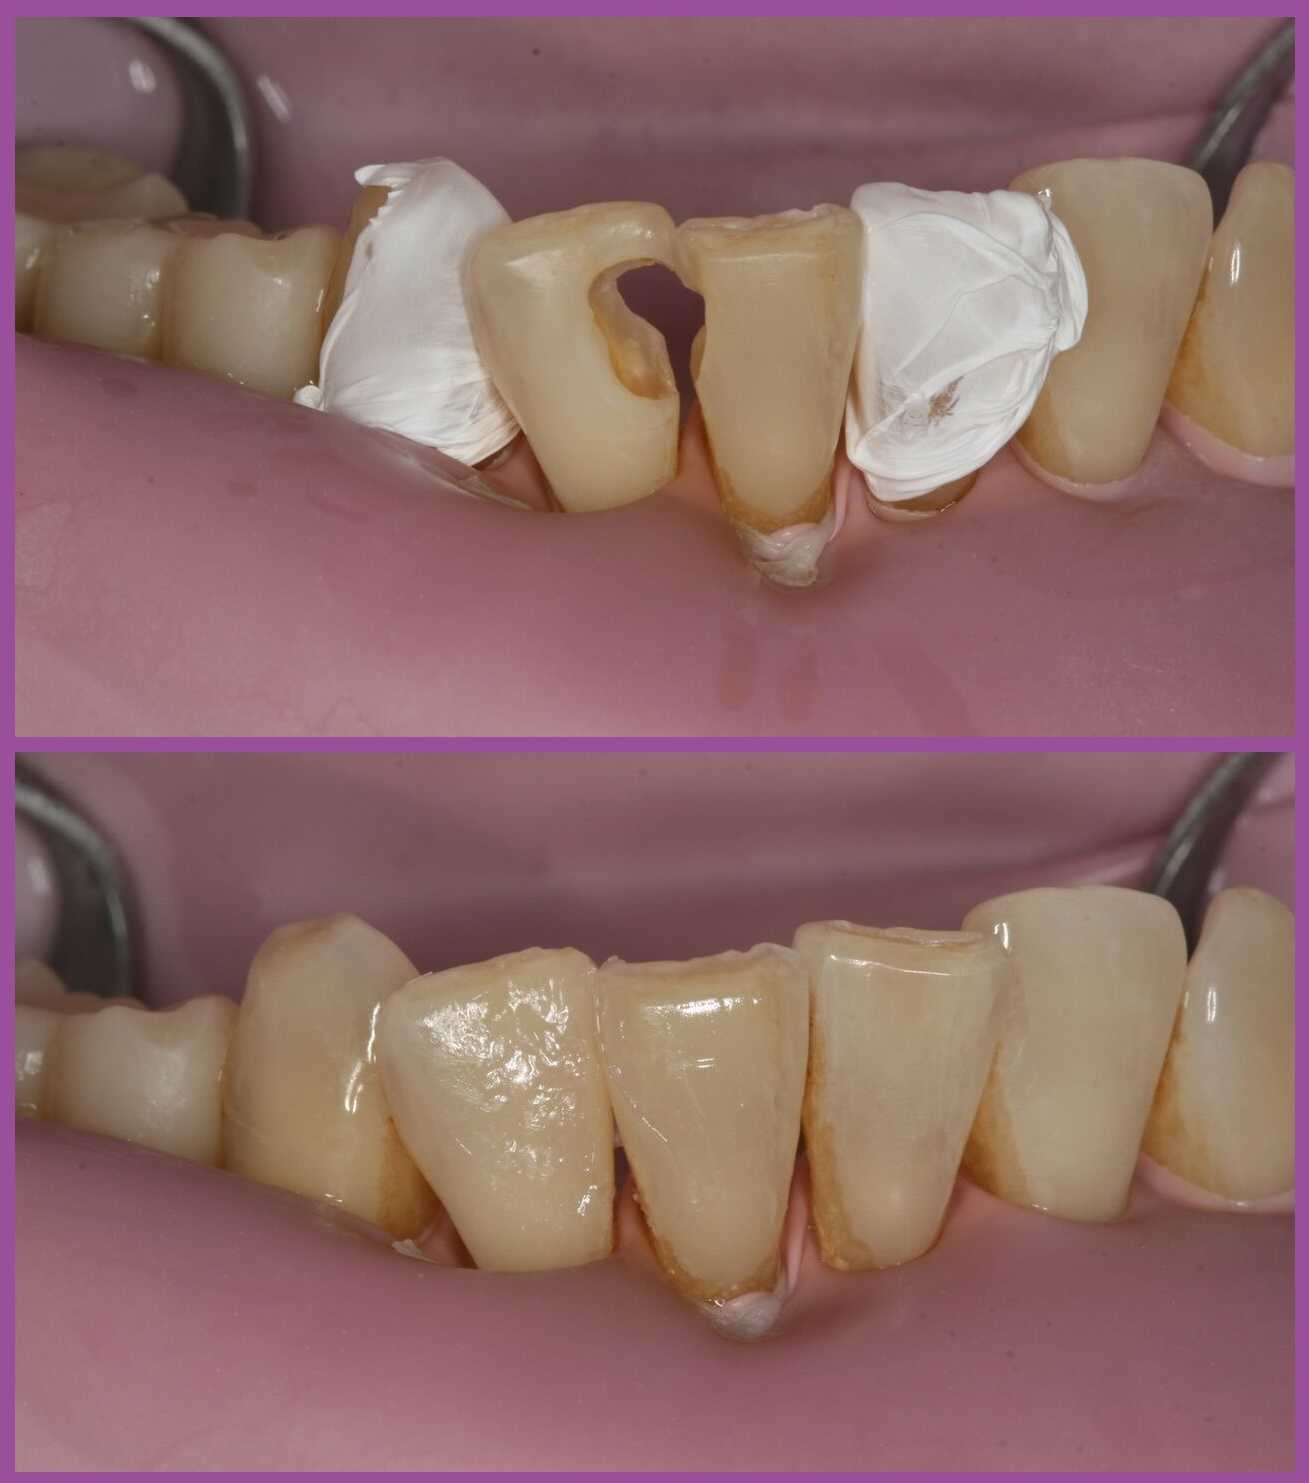

A fenti képen jól megfigyelhető a foganyag hiánya. (Természetesen már a kezeléshez előkészített fogat láthat, amelyekből eltávolítottak minden károsodott foganyagot.)

Amalgámtömés cseréje láthatatlan tömésre

Egy ilyen fogtöméscsere eredményét láthatja a fenti képen is.